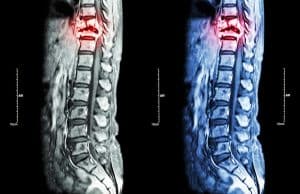

What Are the Four Types of Spinal Cord Injuries?

Many people with loved ones diagnosed with a spinal cord injury are often surprised to learn that there are four different types of spinal injuries. Their understanding of the injury is limited, typically recognizing that their loved one is experiencing significant pain and unable to perform the same activities that they were capable of prior to their injury. However, it is important to remain informed and understand the various types of spinal cord injuries to prepare for potential complications that may arise.

- Sacral spinal cord injuries: A sacral spinal cord injury typically occurs within the area between the tailbone and the lumbar spine, known as the coccyx. The coccyx area consists of five bones, each with its own set of nerves. Accordingly, the nerves may be affected in various ways depending on which bones are injured or damaged within this area. This may result in chronic pain and inability to control certain organs. The organs most commonly affected by sacral spinal cord injuries are the bowels, sex organs, and the bladder. Individuals suffering from this type of injury may experience difficulties controlling their bladder or bowels. Additionally, it is not uncommon for individuals to lose some leg or hip function because of a sacral spinal cord injury. However, these individuals should typically maintain the ability to walk and get around.

- Cervical spinal cord injuries: Cervical spinal cord injuries occur in the upper portion of the spinal cord. More specifically, these injuries are common in the neck area which consists of seven vertebrae. Since cervical spinal cord injuries are in close proximity to the brain, they are generally the most severe types of spinal cord injuries. Consequently, a diagnosis of this type of spinal cord injury often results in the individual learning they are paralyzed from the neck down—a condition known as quadriplegia—rendering the individual unable to move their arms or legs.

- Lumbar spinal cord injuries: Lumbar spinal cord injuries occur in the lower region of the spinal cord, just above the sacral area. The lumbar portion of the spinal cord consists of five vertebrae and is responsible for bearing most of your bodyweight. Accordingly, the vertebrae in the lumbar are much larger than vertebrae in other parts of the human spine. Individuals diagnosed with a lumbar spinal cord injury typically experience some loss of function in their legs and hips, while their upper body remains unaffected. Individuals with lumbar spinal cord injuries commonly face issues with bladder or bowel control, and they may also experience some difficulties with mobility.

- Thoracic spinal cord injuries: Thoracic spinal cord injuries affect the middle and upper portions of the back, spanning across 12 vertebrae. Injuries to the first five vertebrae in this area can lead to issues in the chest, mid-back, and abdomen. This can result in difficulties with lung function, rib and diaphragm muscles, and other respiratory support muscles. On the other hand, injuries to the last seven vertebrae in the thoracic spinal cord can impact an individual’s ability to sit up straight and maintain balance, making tasks like coughing or clearing airways difficult. Thoracic spinal cord injuries frequently lead to severe complications, such as muscle weakness, fevers, chronic back pain, sexual dysfunction, and loss of bladder or bowel control. Paraplegia is also common among those who have a thoracic spinal cord injury, which means that they cannot walk or move their legs.